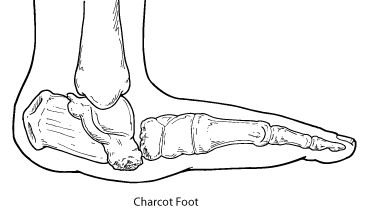

Charcot foot is a condition causing weakening of the bones in the foot that can occur in people who have significant nerve damage (neuropathy). The bones are weakened enough to fracture, and with continued walking the foot eventually changes shape. As the disorder progresses, the joints collapse and the foot takes on an abnormal shape, such as a rocker-bottom appearance.

Charcot foot is a very serious condition that can lead to severe deformity, disability, and even amputation. Because of its seriousness, it is important that patients with diabetes, a disease often associated with neuropathy take preventive measures and seek immediate care if signs or symptoms appear.

In some cases, the Charcot deformity may become severe enough that surgery is necessary. The foot and ankle surgeon will determine the proper timing as well as the appropriate procedure for the individual case.